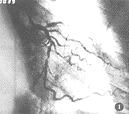

图8 “胸痛”病人,ECG有ST-T段缺血改变,平板试验(-),冠脉造影正常

临床医师经常将胸闷、胸痛伴心电图ST-T段缺血性改变或有冠心病危险因素时误诊为“冠心病”而做CAG检查,其阳性率从0%~36%,差别很大[7,8],本文C组102例均为“冠心病”可疑者,都做过ECG检查有ST-T段缺血表现,部分还作过平板运动试验,不少病例造影前都按“冠心病”治疗,但经CAG检查阳性率仅11.7%,阴性达88.2%(图8),蒲氏[8]对27例阵发性房颤病人行CAG检查,发现9例(33%)年龄较大房颤病人CAG有病理性狭窄表现,认为对这些病人不应轻易作出有无冠心病的诊断,有条件者应行CAG检查,以免造成漏诊或误诊。我们认为对“胸痛组”病人应先行无创性检查,以避免不必要的有创检查,如仍无法确诊,再行CAG检查。